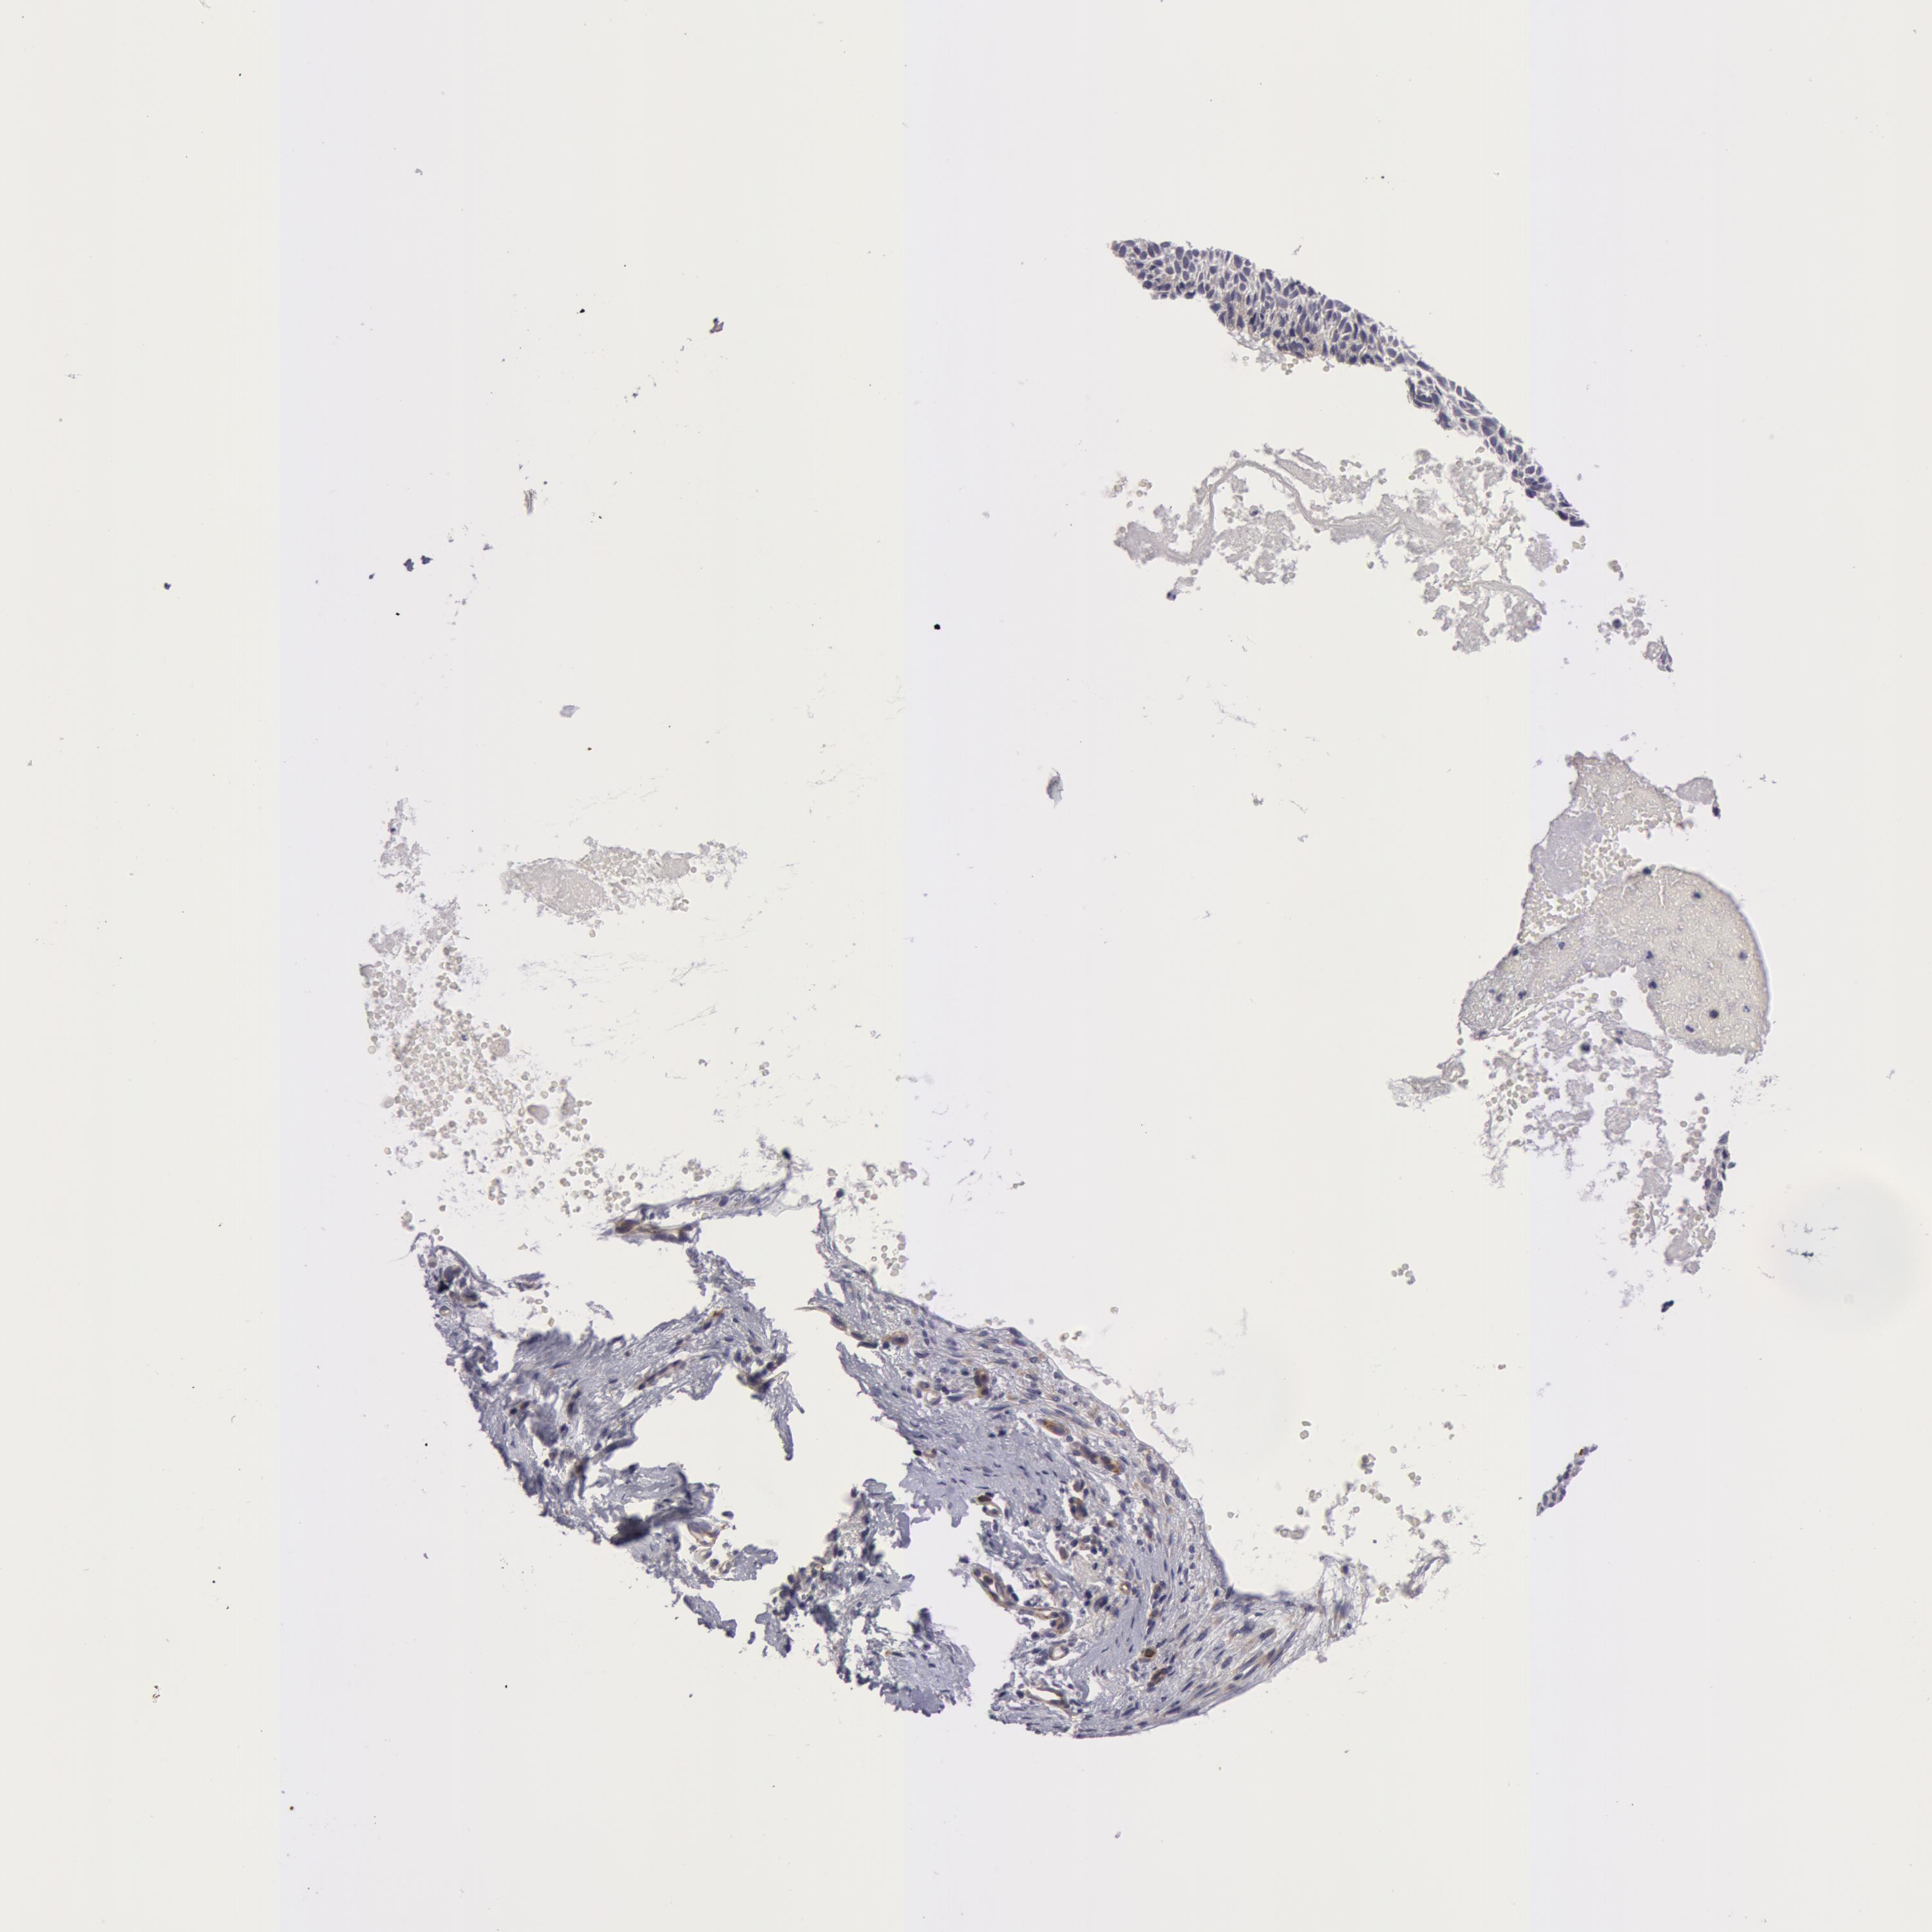

SKIN CANCER - Protein expressioni

A mouse-over function shows sample information and annotation data. Click on an image to view it in a full screen mode. Samples can be filtered based on level of antibody staining by selecting one or several of the following categories: high, medium, low and not detected. The assay and annotation is described here.

Antibody stainingi

Antibody staining in the annotated cell types in the current human tissue is reported as not detected, low, medium, or high, based on conventional immunohistochemistry profiling in selected tissues. This score is based on the combination of the staining intensity and fraction of stained cells.

Each image is clickable and will lead to virtual microscopy that enables deeper exploration of all samples and also displays staining intensity scores, fraction scores and subcellular localization as well as patient and tissue information for each sample.

Antibody HPA001554

Staining

High

Medium

Low

Not detected

Intensity

Strong

Moderate

Weak

Negative

Quantity

>75%

75%-25%

<25%

None

Location

Nuclear

Cytoplasmic/membranous

Cytoplasmic/membranous,nuclear

Squamous cell carcinoma, NOS

Basal cell carcinoma